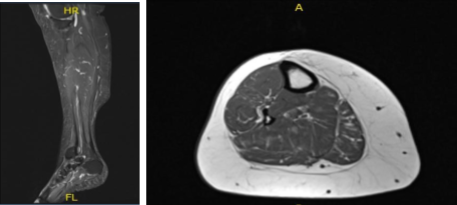

MRI- Right Calf Non-contrast

The patient is here for a follow up with an MRI of the right calf to review. Results showed no evidence of tibial stress fracture or stress reaction. Calf musculature is normal.

Degenerative changes within the knee as well as a small popliteal cyst are better appreciated on the recent knee MRI. Limited evaluation of the ankle demonstrates chronic plantar fasciitis and a partial tear at the origin of the central cord.